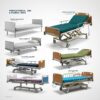

patient Examination table buy online

Examination Beds for Specialized Medical Procedures

Examination beds designed for specialized medical procedures include diagnostic treatment beds, clinical procedure beds, and medical observation couches. These beds are Hospital in hospitals and clinics to perform specific medical tasks such as diagnostic assessments, medical evaluations, and patient treatments. Healthcare procedure beds and patient care beds are essential for providing targeted medical care, while Examination stretchers and diagnostic assessment beds are Hospital for more intensive medical investigations and treatments